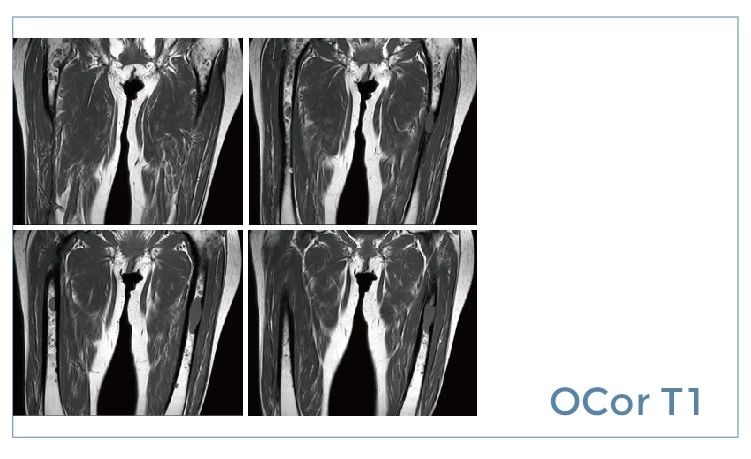

【朗润影像档案】磁共振影像病例分享(编号20190802)